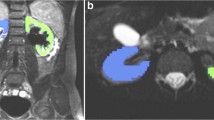

For the DTI analysis and segmentation, we used software package Diffusion Toolkit version 0.6.4.1 and TrackVis version 0.6.0.1 (www.trackvis.org) [18]. Tractography was reconstructed using a deterministic fiber tracking algorithm with a minimum fractional anisotropy threshold of 0.10 and a maximum turning angle of 55° between two adjacent voxels based on published parameters for renal tractography [4]. A postdoctoral fellow with 5 years of experience in DTI research (J.D.) used TrackVis to draw regions of interest (ROIs) covering the entire volume of the renal parenchyma, excluding the collecting system by evaluating the diffusion-weighted images, ADC and fractional anisotropy maps (Fig. 2). These images were used to avoid problems of alignment related to patient motion in-between sequences. The ADC and fractional anisotropy values based on the ROI data, and the mean length and volume of the tracks based on the fiber track data, were exported. An additional ROI in the mid-axial plane of each kidney (Fig. 2) was drawn for qualitative evaluation of the scalar fractional anisotropy tractography maps.

Renal region of interest (ROI) placement in the left kidney of a 5.5-year-old boy with ureteropelvic junction obstruction. a Axial T2-W image shows grade 3 pelvicalyceal dilatation. b Axial diffusion-weighted (b=400 mm/s2) image depicts the limits of the renal parenchyma (arrows). c Axial apparent diffusion coefficient map and (d) axial fractional anisotropy map used in conjunction with one another to avoid placing the ROI within the pelvicalyceal system. Note the corticomedullary differentiation in the fractional anisotropy map (arrowhead). Voxel dimensions for images (b, c, d) are 2 × 2.7 mm in plane with 4-mm section thickness and are used for placement of ROI only. e ROI placement is depicted in pink. f Coronal tractographic image of the post-processed kidney

Corticomedullary differentiation on the scalar tractography fractional anisotropy maps. a Normal left kidney in a 2.3-year-old boy with congenital hydronephrosis and suspicion of ureteropelvic junction (UPJ) obstruction. b Left kidney with UPJ obstruction in an 8.8-year-old boy with grade 3 pelvicalyceal dilatation. Note that on T2-W images the corticomedullary differentiation is still preserved for both patients (arrows in a and b). c Scalar fractional anisotropy tractography map of the patient in (a) shows an increased fractional anisotropy value at the location of the renal pyramids with maximum fractional anisotropy (yellow and red, arrow) in the center of the pyramids and relatively decreased fractional anisotropy values in the renal cortex (blue). d Scalar fractional anisotropy tractography map of the patient in (b) shows no clear differentiation of the renal cortex and medulla (arrow)